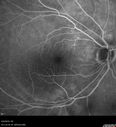

63 year old female She noticed a new thumbprint on her right eye with decreased vision March 10, 2019.  She waited a few days.  She was an eye institute where they said it was a cataract and scheduled for surgery.  She asked why if the cataracts are the same there was trouble with the one eye. He agreed and sent her to his retina specialist who noticed a problem and suggested a referral out. She has no health problems otherwise but has not been to a doctor lately.   VA OD: Dcc20/125 PHNI Ncc20/400 VA OS: Dcc20/50 PH20/32 NccJ5 IOP: TP: OD:23 OS:22 Time:15:56

Lung Cancer Metastasis to Right Eye372 views63 year old female with vision loss for 6 weeks. She had been scheduled for cataract surgery and then a tumor was found. She was ultimately diagnosed with lung cancer. Vision is 20/10000000